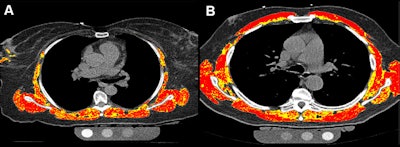

- Lung cancer screening reporting reveals incidental finding risk classesby Liz Carey on January 6, 2026 at 7:40 am

Researchers tracked seven prespecified "S modifiers," or clinically significant incidental findings.